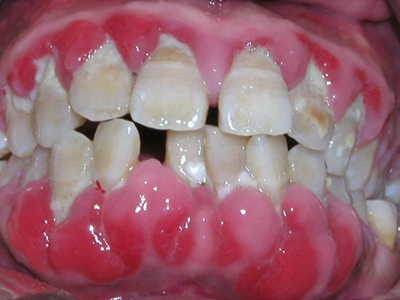

牙龈炎是发生于牙龈组织的炎症,患者可出现牙龈出血伴肿胀、发红、正常形态改变和偶尔不适等症状。本病主要由口腔卫生状况差导致,包括口腔不洁、牙菌斑等,诊断依据临床检查,治疗包括专业牙齿清洁和加强家庭口腔卫生。

牙龈炎可先引起牙齿与牙龈之间的沟(龈沟)加深,然后牙龈充血,炎症围绕一个或多个牙齿,伴牙龈乳头肿胀和易出血。一般无痛,可自行消退,也可维持轻度炎症数年。

牙龈炎常见的病因是口腔卫生差,不良的口腔卫生使牙菌斑沉积于牙齿与牙龈之间,造成龈沟加深,另外牙结石、不良修复体等也可造成牙龈炎的发生。

牙龈炎患者可通过改善口腔卫生控制疾病,同时使用抗菌漱口液,如复方氯己定含漱液,并进行彻底的洁治处理。必要时,重新修整修复体的不良外形,并祛除局部刺激因素。